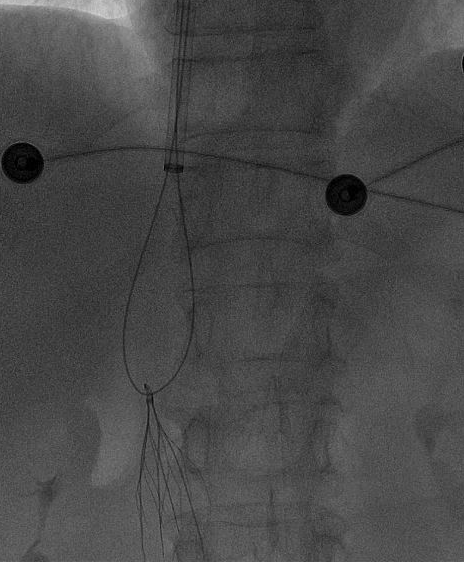

一切准备就绪后,田轩带领介入诊疗团队为阿婆实施下腔静脉滤器取出术。

术中,团队在影像设备的精准引导下,娴熟操作介入器械,精准定位倾斜的滤器,避开血管周边组织,逐步完成滤器的调整、抓取与取出操作。

整个手术过程十分顺利,未出现任何血管损伤等意外情况,这枚让阿婆和家属忧心许久的“困难”滤器被成功取出,术后阿婆生命体征平稳,身体状况良好。